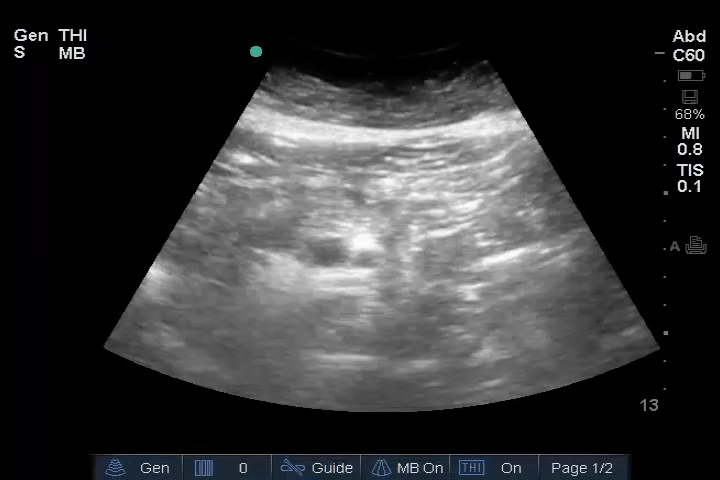

Abdomen: Normal – no free fluid.

20_Abdomen_RUQ_Perihepatic – Normal

22_Abdomen_LUQ_Perisplenic – Normal

23_Abdomen_Pelvic_Sagittal – Normal

24_Abdomen_Pelvic_Transverse – Normal

25_Abdomen_Aorta_Transverse – Normal